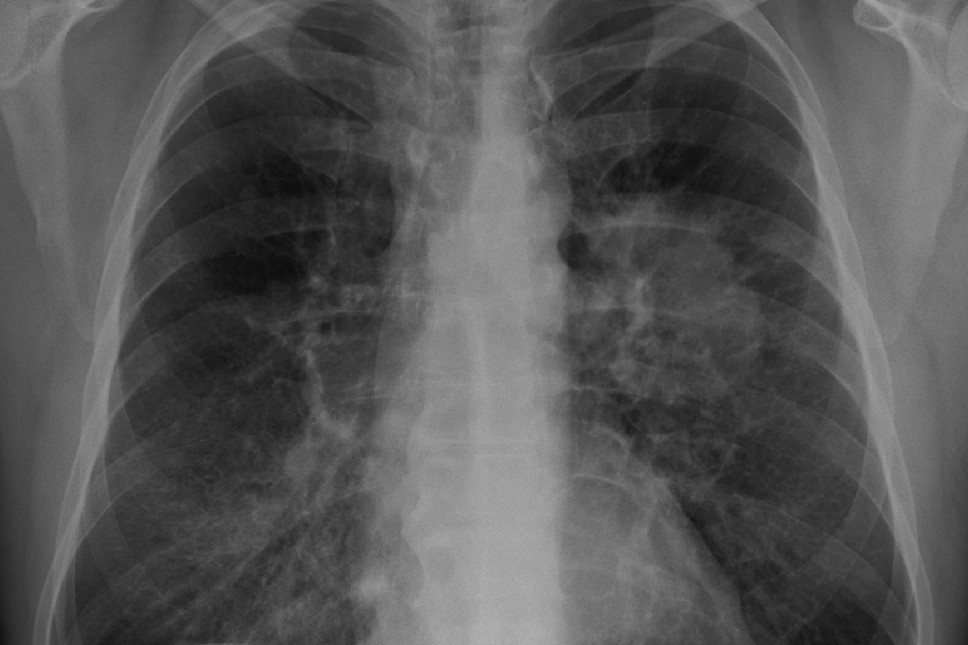

Program prevence rakoviny plic, který v Česku běží na prevenceproplice.cz, dokáže zachytit problém dřív, než se ozve kašel. Je určen lidem ve věku 55 až 74 let, kteří kouří nebo kouřili déle než 20 let. Vyšetření pomocí nízkodávkového CT umí odhalit nádor ještě ve chvíli, kdy je léčba účinná a šance na uzdravení vysoká.